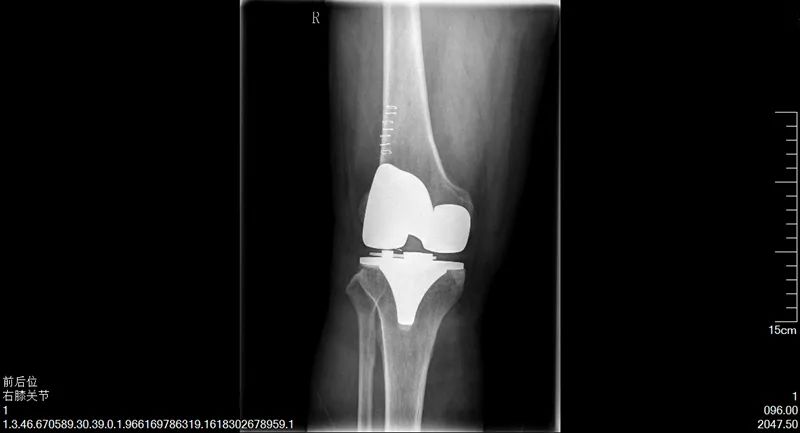

陳阿姨的故事,說來還要將時間追溯至十年前,陳阿姨常年操持家中的生意,雙膝落下了問題,時常疼痛難忍,后來甚至發(fā)展至不能正常行走。這時,鄰居常大哥告訴她,可以試試到市第一人民醫(yī)院看看。隨即,陳阿姨來到了我院骨科二病區(qū)找到了楊勇主任,做了雙側(cè)人工全膝關(guān)節(jié)置換術(shù),術(shù)后恢復(fù)得非常好,雙腿和正常人無異,既不疼了,也能站直了。時至今日,陳阿姨說她的腿依然健康如初,每天可以去跳廣場舞,生活質(zhì)量得到了顯著提高。

手術(shù)后